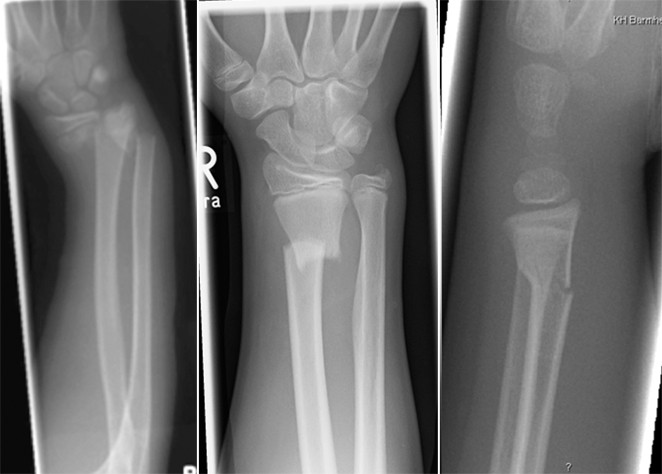

File Collesfracture Jpg Wikimedia Commons

Figure 2 Frakturen Des Unterarms Beim Kind Springerlink

Colles Fracture Causes Presentation And Management Kenhub